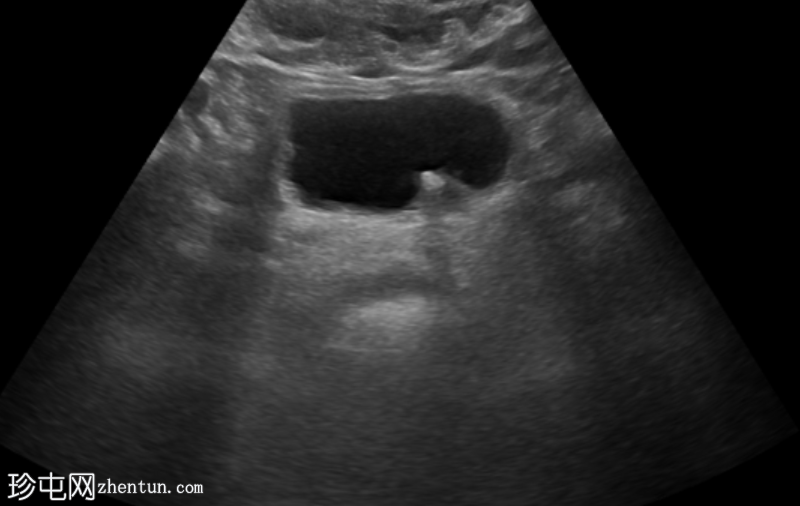

超声

检查

超声显示左侧轻度肾积水,由膀胱输尿管连接处一枚7毫米的远端输尿管结石阻塞所致,输尿管射流正常。